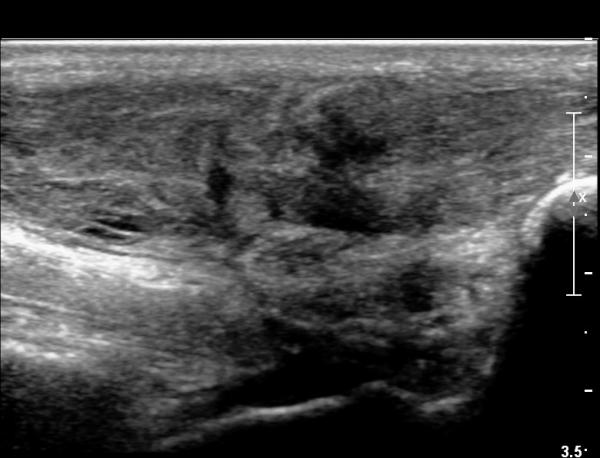

2018³â  1¿ù 30ÀÏ ÃßÀû°Ë»ç

¾ÆÅ³·¹½º°Ç Àú¿¡ÄÚºÎÁ¾ÀÌ °¨¼ÒµÇ°í  ÆÄ¿­ºÎÀ§ Àú¿¡ÄÚ°¡ È£ÀüµÇ¾î

°ÇÀÇ ¼¶À¯¼º¾ç»ó(fibrillar pattern)ÀÌ È¸º¹µÇ°í ±¹¼ÒÀû ¿¬°á¼º ¼Ò½ÇÀÌ »ç¶óÁü(»çÁø 9, 10, 11, 12).